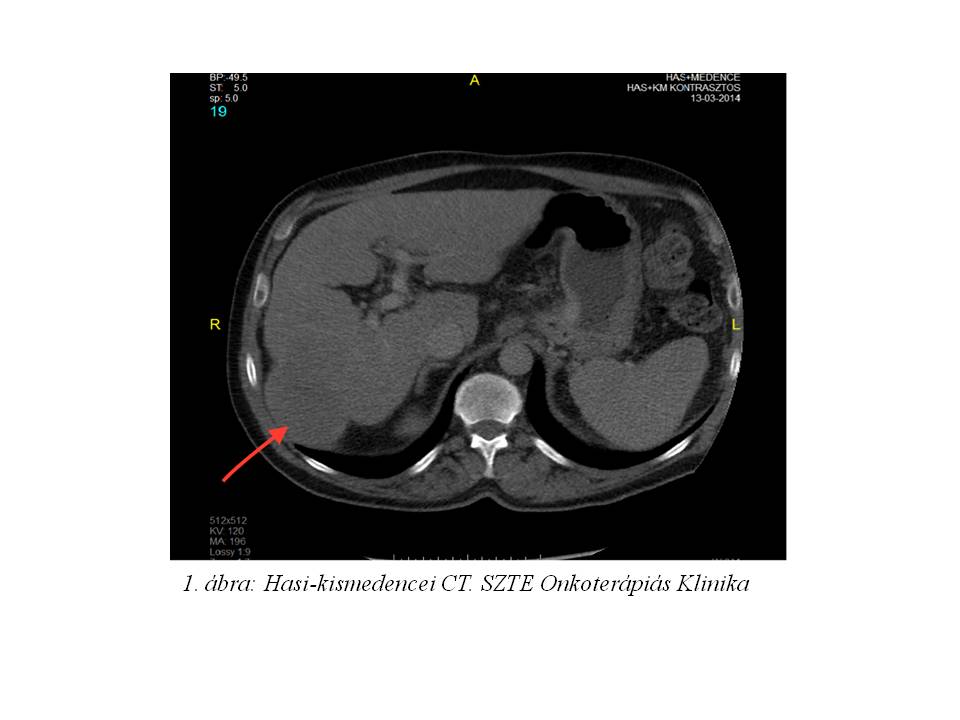

A multidiszciplináris onkoteam döntése alapján sebészi eltávolítás, illetve a jobb vena hepatica érintettsége miatt TACE (transarterialis chemoembolisatio) kezelés nem jött szóba. A vizsgálatok szerint a beteg hepatocelluláris karcinómája BCLC “C” (The Barcelona Clinic Liver Cancer staging) stádiumú volt, a hepatikus funkciók szempontjából pedig a Child-Pugh pontrendszer besorolása szerint az “A” osztályba tartozott, így sorafenib (Nexavar) monoterápiája indult 2014 áprilisában. A beteg 3 ciklust kapott meg. Azt ezt követően készült kontroll staging vizsgálatok azonban a betegség RECIST 1.1 szerinti 36%-os progresszióját igazolták. Az AFP szint 1388 µg/L-re emelkedett. A kezelt HCC nagyobbik góca a progresszió során áttörte a máj dorsolaterális tokját, mely a megfelelő régióban tapintható terimét hozott létre (2. ábra). A progresszió miatt a beteg sorafenib kezelése 2014 júliusában felfüggesztésre került.